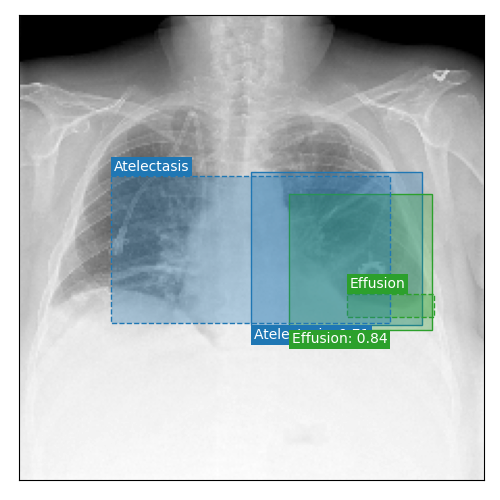

Qualitative Results

As shown in Fig. 4 Loc-ADPD detects cardiomegaly almost perfectly, as it is always exactly localized at one anatomical region. Other pathologies are detected but often with too large or too small boxes as they only cover parts of anatomical regions or stretch over several of them, which cannot be completely corrected using WBF. Detection also works well for predicting several overlapping pathologies. For qualitative comparisons between Loc-ADPD and MIL-ADPD, we refer to Appendix 0.B.